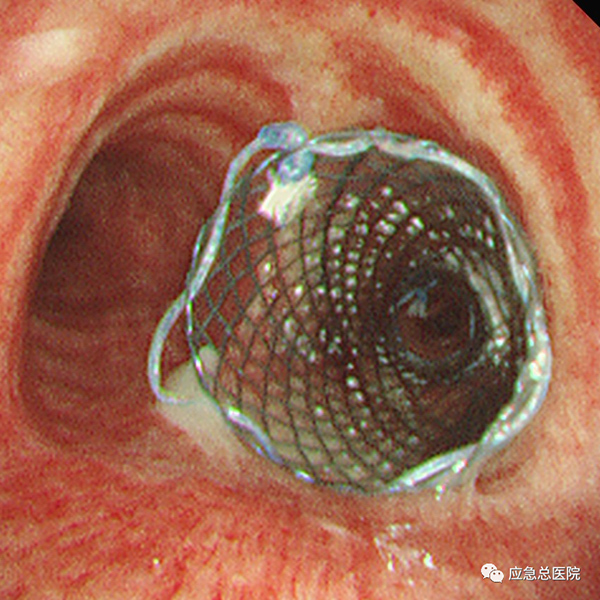

(1)经气道介入技术:硬质支气管镜、氩气刀、二氧化碳冷冻、球囊扩张、激光、低温等离子射频、微波、气道支架置入及取出、放射性粒子植入、局部药物注射、光动力治疗、各类气道瘘口的封堵等,全面解决患者的气道梗阻及气道瘘问题。同时对慢阻肺(COPD)终末期患者予以支气管镜下单向活瓣肺减容术、热蒸汽消融肺气肿减容术,并对难治性哮喘患者行支气管热成形术,提高患者生活质量。

气管镜下支架置入手术可以用于食道癌、肺癌、甲状腺癌等各种肿瘤引起的气道狭窄;其他疾病所致的气管、支气管瘘等良性气道狭窄。可以有效缓解患者气急、胸闷等呼吸困难症状,从而提高患者的生活质量,并为后续治疗提供宝贵机会。与外科手术相比,气管镜下支架置入技术具有不开刀、创伤小、操作简便、安全性高、术后恢复快、并发症少等显著优点。对于无法手术及无法耐受手术的恶性肿瘤患者,该方法创伤小,出血少,病人耐受性较好,可缓解症状,达到姑息治疗的目的。